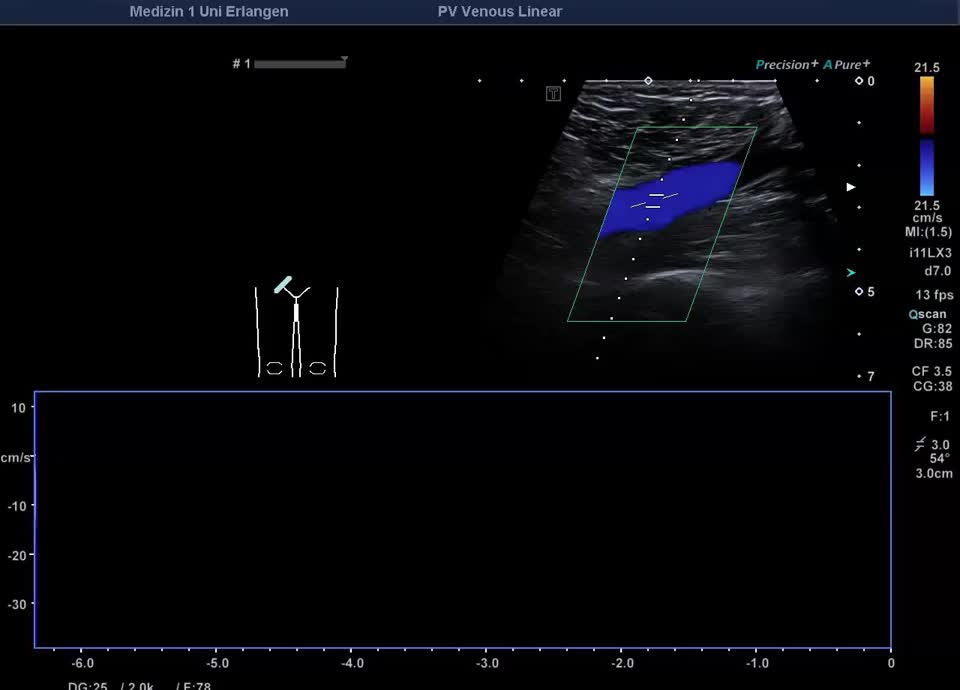

Normalbefunde

• Regelrechtes Flussprofil V. iliaca externa (PW-Dopplervideo)

• Flussprofil V. iliaca externa Valsalva-Manöver (PW-Doppler)

• Regelrechtes Flussprofil V. iliaca externa (Farbdopplervideo)